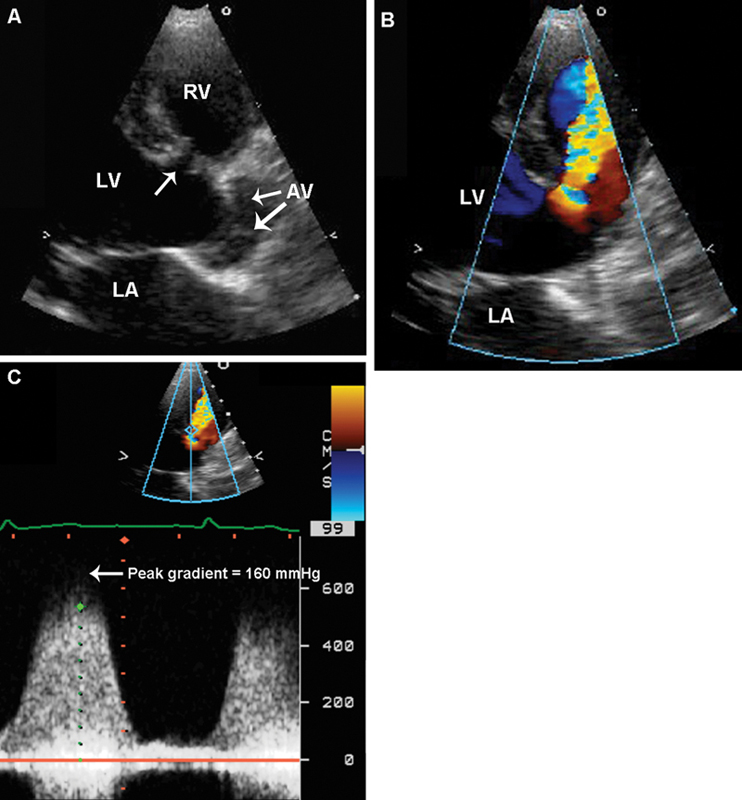

فحوصات تشخيصية لبعض امراض القلب والشرايين التاجية